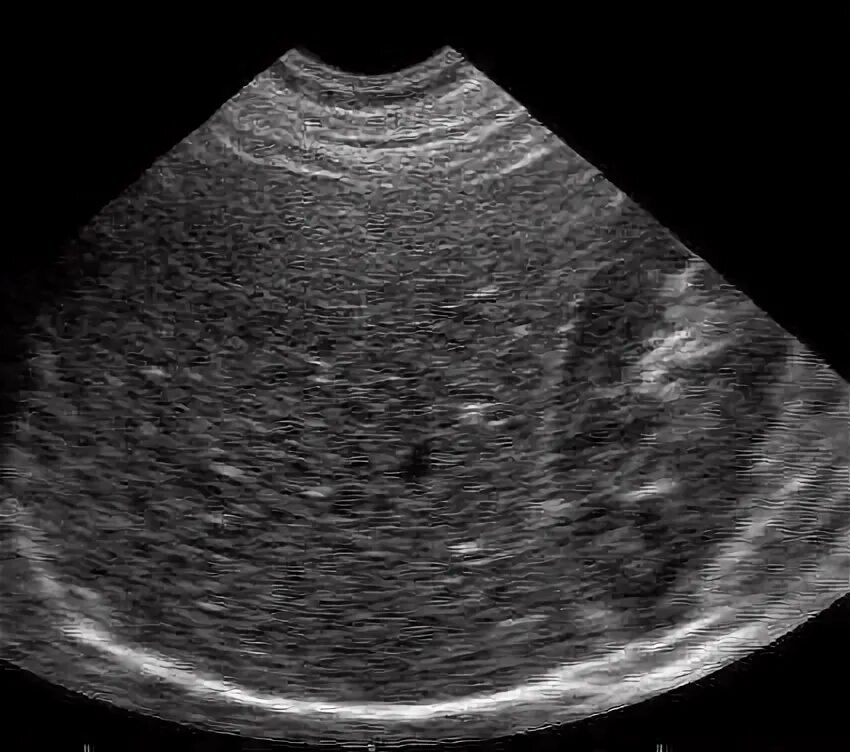

Гиперэхогенные структуры на узи. мелкие гиперэхогенные структуры в почках на узи. гиперэхогенная структура паренхимы печени. гиперэхогенные включения в печени на узи.Гиперэхогенные образования в печени на узи.Доброкачественные опухоли печени на узи. гиперэхогенные образования в печени на узи. гиперэхогенные включения в печени на узи.Узи селезенки гиперэхогенные образования. гиперэхогенное образование в печени. гиперэхогенные образования в печени на узи. гиперэхогенные структуры на узи.Гиперэхогенные включения в печени на узи. узи селезенки гиперэхогенные образования. гиперэхогенное образование в селезенке.Гиперэхогенное включение в печениГиперэхогенное образование в печени на узи что это такое. газ в портальной системе печени на узи. гиперэхогенные включения в печени на узи. гиперэхогенные точечные включения в селезенке на узи.Гиперэхогенная печень. гиперэхогенные образования в печени. гиперэхогенная печень на узи. гиперэхогенное образование в печени на узи что это такое.Гиперэхогенные включения в печени на узи. холангит на узи.Узи анатомия почек. гиперэхогенные линейные структуры. точечные гиперэхогенные включения в печени. гиперэхогенные включения в миометрии.Гиперэхогенное включение в печениТочечные гиперэхогенные включения в печени. гиперэхогенное образование в почке что это. симптом гиперэхогенных пирамид в почках на узи. гиперэхогенные тяжи на узи.Гиперэхогенные структуры на узи. гиперэхогенные включения без акустической тени. узи селезенки гиперэхогенные образования. гиперэхогенное образование в печени на узи что это такое.Гиперэхогенные включения в печени на узи. амебный абсцесс печени на узи. гиперэхогенный очаг в печени. неоднородное образование в печени на узи.Метастатическое поражение печени узи. образования печени на узи. гиперэхогенные образования.Гиперэхогенное включение в печениГиперэхогенные образования. гиперэхогенное образование на узи. гиперэхогенные образования в печени.Метастазы в печень гиперэхогенные узи. гиперэхогенное образование. гиперэхогенные включения. множественные гиперэхогенные включения в печени.Гиперэхогенные включения поджелудочной железы. гиперэхогенные включения в печени на узи. узи множественные гиперэхогенные. кальцинаты в простате на узи.Подкапсульная гематома печени на узи. гиперэхогенные образования в печени. гиперэхогенные включения в печени. гиперэхогенное образование в печени по узи.Гиперэхогенные образования в печени на узи. гепатоцеллюлярная аденома печени узи. гиперэхогенный очаг в печени на узи. очаговый липоматоз печени узи.Гиперэхогенные образования. множественные гиперэхогенные образования. гиперэхогенные образования в печени. образование брюшной полости узи.Гиперэхогенное включение в печениГиперэхогенная печень. гиперэхогенный желчный пузырь. гиперэхогенное образование в желчном пузыре. гиперэхогенные образования в печени.Узи желчного пузыря гиперэхогенные. гиперэхогенный желчный пузырь узи. гипоэхогенное образование в желчном пузыре. гиперэхогенное образование в желчном пузыре.Гиперэхогенное включение в печениГиперэхогенный полип эндометрия. гиперэхогенное. множественные гиперэхогенные образования.Гиперэхогенное включение в печениГиперэхогенные образования в печени на узи. гипоэхогенные образования в печени метастазы. гипоэхогенное образование при узи печени.Гиперэхогенное включение в печениГиперэхогенное неоднородное образование в печени. гиперэхогенные структуры. в полости матки гиперэхогенное образование. гиперэхогенные линейные структуры.Гиперэхогенные включения в печени на узи. гиперэхогенный очаг в мочевом пузыре.Гиперэхогенные участки на узи. гиперэхогенное включение. гиперэхогенные включения в яичнике.Гиперэхогенное включение в печениКонкремент в мочевом пузыре узи протокол. линейное гиперэхогенное образование. гиперэхогенное образование на узи.Синдром гиперэхогенных пирамид почек узи. узи селезенки гиперэхогенные образования. гиперэхогенные включения в печени на узи. образование почки на узи в паренхиме.Гиперэхогенное образование на узи. узи анатомия почек. точечные гиперэхогенные включения в печени.Сонограмма поджелудочной железы. кольцевидная поджелудочная железа узи. гиперэхогенное образование поджелудочной железы узи. гиперэхогенные включения в печени на узи.Гиперэхогенная структура на узи. гиперэхогенное образование на узи. гиперэхогенное образование диаметром 21 мм. гиперэхогенные включения до 3-4 мм.Гиперэхогенные включения. гиперэхогенные включения в матке. гиперэхогенное точечное включение. гиперэхогенные включения в цервикальном канале.